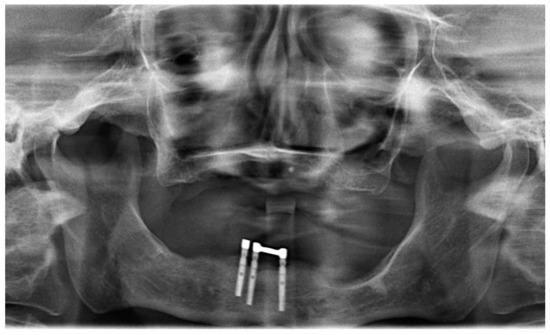

Figure 1.

Preoperative panoramic radiograph with complete edentulism in the maxilla and failing implants in the mandible.